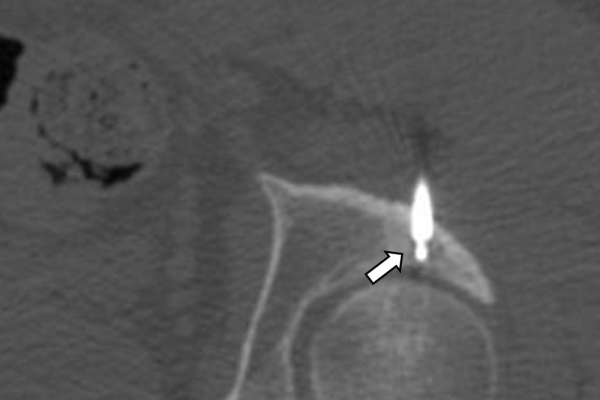

Πρόκειται για την πιο σύγχρονη τοπική θεραπεία όγκων του ήπατος, του νεφρού, του πνεύμονα, των οστών και των όγκων μαλακών μορίων. Παθοφυσιολογικά βασίζεται στην τοπική καταστροφή των καρκινικών κυττάρων με τη δημιουργία ιδιαίτερα υψηλών θερμοκρασιών εντός του όγκου. Αυτό επιτυγχάνεται με τοποθέτηση ειδικών ηλεκτροδίων εντός του όγκου υπό ακτινολογική καθοδήγηση (αξονικός τομογράφος ή υπέρηχος). Τα ηλεκτρόδια αυτά παράγουν υψηλή θερμοκρασία είτε με τη βοήθεια ραδιοσυχνοτήτων (RFablation), είτε με τη βοήθεια μικροκυμάτων (MWablation) και προκαλούν πηκτική νέκρωση των καρκινικών κυττάρων χωρίς να επηρεάζουν τα φυσιολογικά κύτταρα.Το αποτέλεσμα είναι μόνιμο.